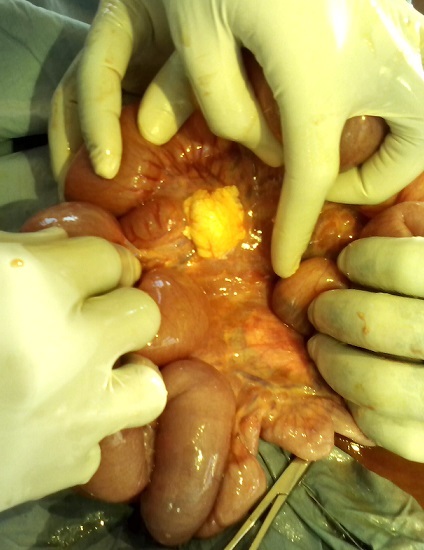

L'abdomen entièrement ballonné, les ondes péristaltiques de lutte spontanément visibles sous la peau et exacerbées par la chiquenaude et plus marquées en sus ombilicale. L'abdomen était souple, tympanique dans son ensemble et des bruits hydroaériques en sus ombilical et paraombilcal gauche et un silence dans la région hypogastrique et la fosse iliaque droite. Le boudin d'invagination n'a pas été palpé. Au toucher rectale l'ampoule rectale était vide, le Douglas non bombant, non sensible, pas de masse pelvienne palpée et le doigtier propre. La diurèse à son admission en chirurgie n’était pas connue. Le diagnostic différentiel était une occlusion intestinale haute sur paquet d'ascaris ou sur invagination intestinale aigue. Nous avons fait couler 750ml de sérum physiologique en 1heure et recueilli 120ml d'urine. Le bilan préopératoire avait donné ce qui suit: Hb 8,7g, Hte 26%, GS O, Rh +, TS 1'00", TC 4'30", GB 14050/mm3, VS 48mm/h, Formule leucocytaire: N 59%, L 41%. Une intervention chirurgicale a été réalisée dont voici le protocole: Laparotomie médiane sus et sous ombilicale de 12cm de long. Le constat: dilatation importante du grêle depuis l'angle de Treitz jusqu’à environ 50cm de la jonction iléocoecale, le boudin d'invagination iléoiléale de 10 cm de long à environ 50cm de l'angle iléocoecale (Figure 2), le grêle en aval du boudin d'invagination est aplati. Sur le mésentère il y avait plus de 5 ganglions mésentériques hypertrophiés d'environ 2cm de diamètre, immobiles (Figure 3); parmi ces ganglions mésentériques hypertrophiés il avait une masse de couleur jaune (Figure 3), fluctuante d'environ 3cm de diamètre dont la ponction exploratrice a ramené 2,5cc d'un pus jaune (Figure 4) mal lié homogène qui a été envoyé à la bactériologie. Cette masse jaunâtre ne communiquait pas avec la lumière intestinale. Apres désinvagination, l'anse invaginée a gardé une coloration normale (Figure 3). On a incisé la paroi de cette masse et exciser la membrane pyogène dans son entièreté. On a nettoyé la cavité abdominale avec 1l de sérum physiologique tiède puis assécher la cavité abdominale. La paroi abdominale a été fermée sans drainer la cavité abdominale. La membrane pyogène excisée n'a pas été envoyé à l'anatomopathologie. Le patient a subit une réanimation post opératoire, et une transfusion en post opératoire immédiat. Le retour du transit a eu lieu 48h après. L'antibiothérapie instaurée était Trixon-S (ceftriaxone 500mg et Sulbactam 250mg) 750mg deux fois par jour en IVD en attente des résultats de la pyoculture et antibiogramme. La pyoculture et antibiogramme a révélé la présence d'Enterobacter cloacae sensible à la norfloxacine. L'antibiothérapie a été réajustée à raison de Normet (5ml de suspension contient norfloxacine 100mg et metronidazol 100mg) 7,5ml 2 fois par jour pendant 7 jours. Les suites opératoires étaient bonnes.

Figure 3.

La désinvagination est réalisée: on voit que l'intestin est sain mais sur le mésentère plusieurs ganglions hypertrophiés et une masse jaune (adénite mésentérique suppurée) au sein de ces ganglions